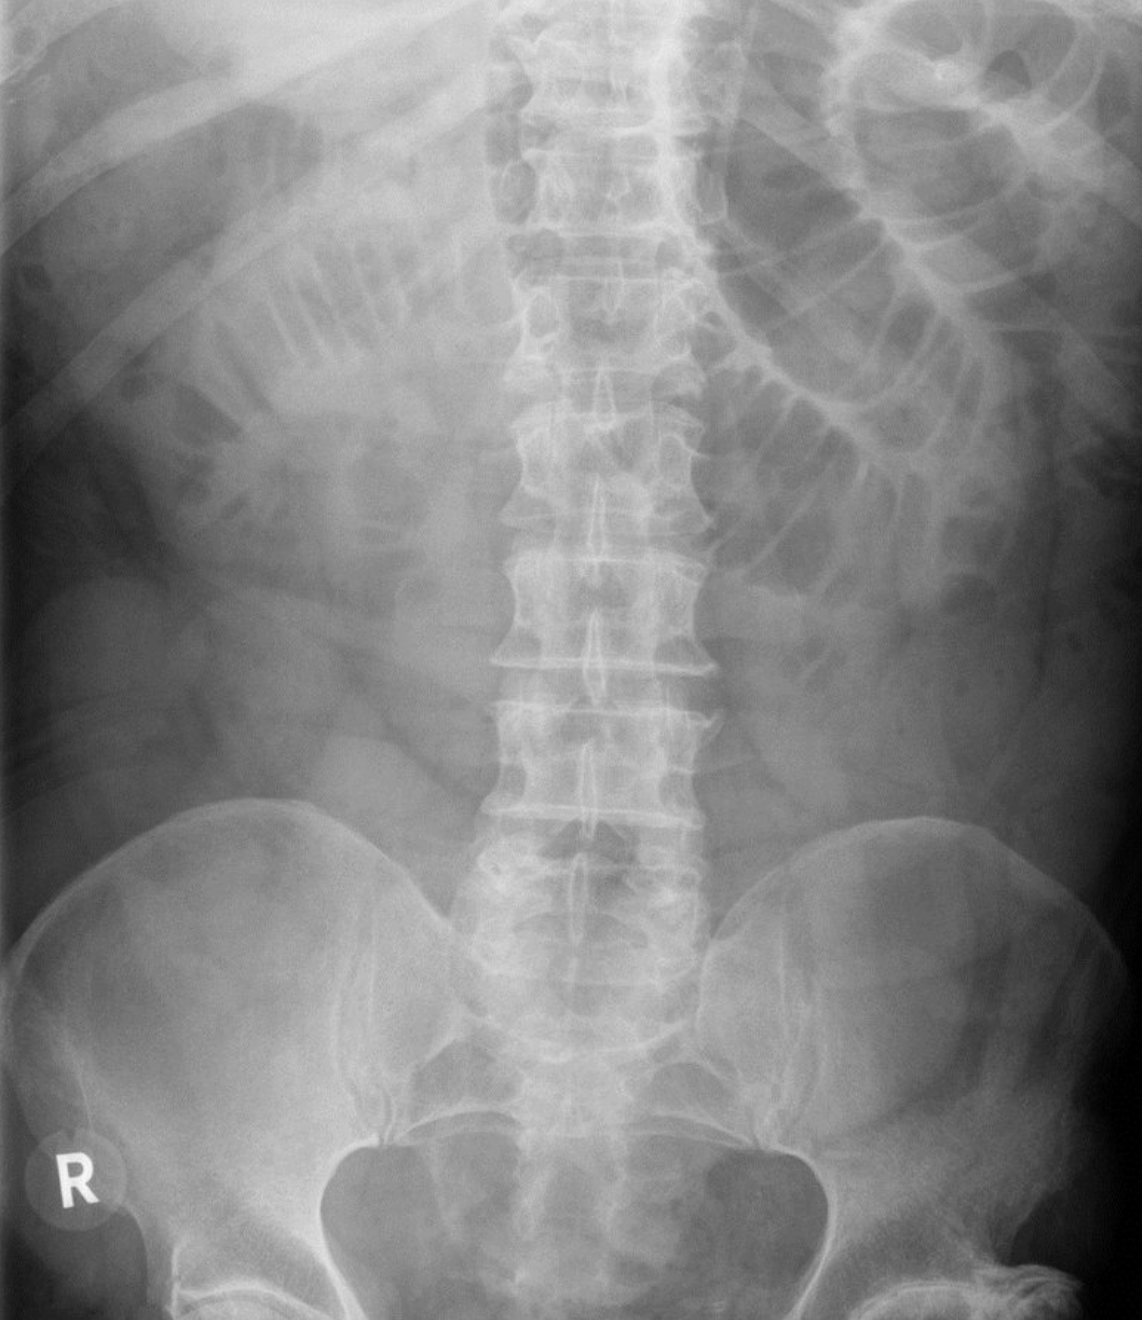

Bilateral hyperinflation and right lung consolidation

X-ray chest (AP view) of a child with viral bronchiolitis and focal pneumonia

Bilateral perihilar peribronchial thickening (examples of bronchi indicated by green lines) is accompanied by hyperinflation with diaphragmatic depression (indicated by white lines and arrow). In the right lung, a superimposed area of consolidation from pneumonia (red overlay) is associated with atelectasis and ipsilateral mediastinal shift (indicated by black arrow).

Black outline: trachea; white dashed line: physiological position of left hemidiaphragm